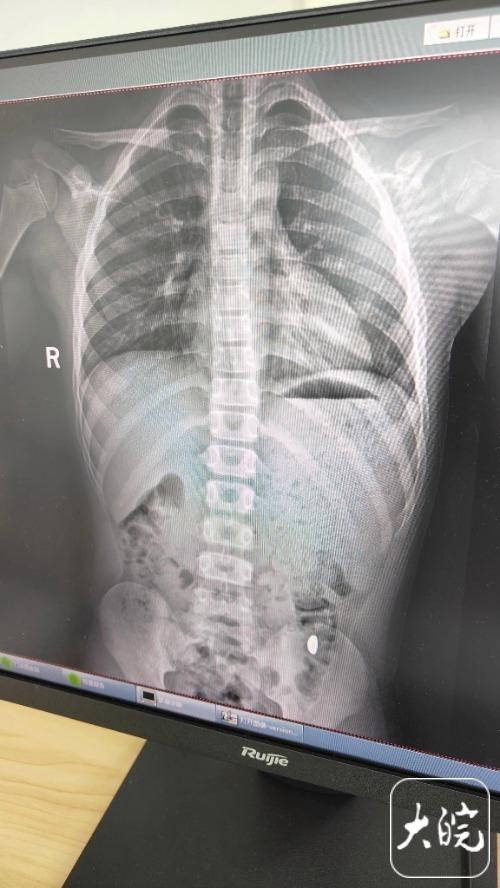

昆山市第五人民医院门诊病历单显示,医生在现病史一栏写着,患儿5天前误吞约10克黄金,期间解2次大便未发现,目前无腹痛、呕吐等症状,诊断结果显示胃内有异物。

右下加亮点为金豆。